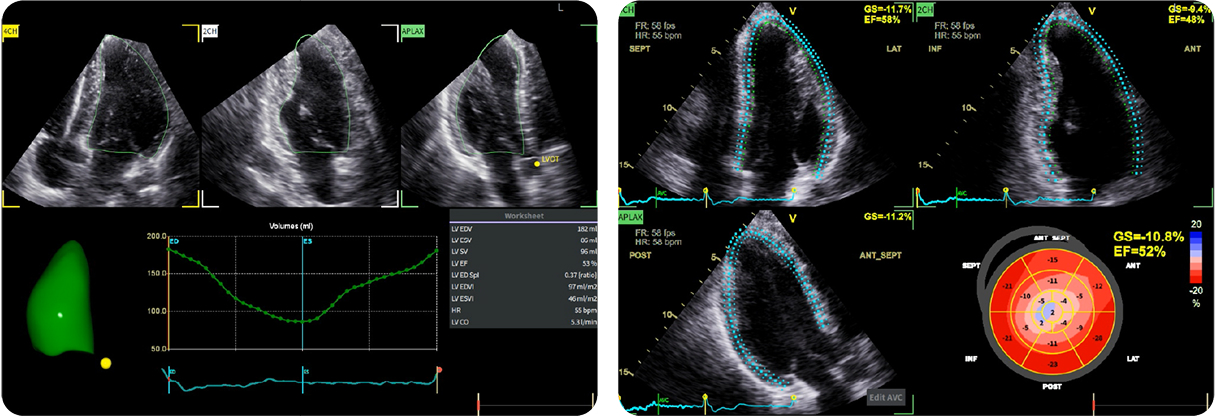

Caso condiviso da Marcello De Santis